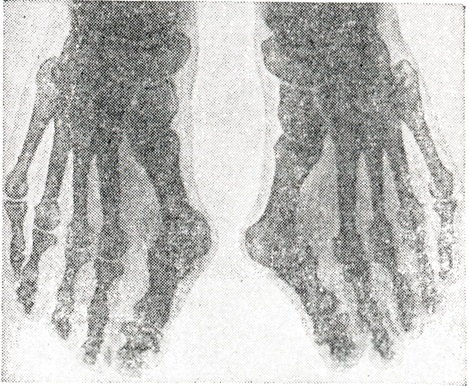

Рис. 1.

Двусторонний hallux valgus (III степень). Большой палец расположен над вторым пальцем и ротирован внутрь.

Вторая степень — угол отклонения большого пальца — 30—39°; боли носят постоянный характер; над головкой I плюсневой кости омозолелость, бурсит (смотри); выражено поперечное плоскостопие формируются молоткообразные пальцы. Третья степень — большой палец отклонён на 40° и более (рисунок 1) и располагается над или под II пальцем и ротирован внутрь; рецидивирующие бурситы в области головки I плюсневой кости; резко выражено поперечное плоскостопие, молоткообразные пальцы. Резко выраженная, запущенная деформация может привести к инвалидности.